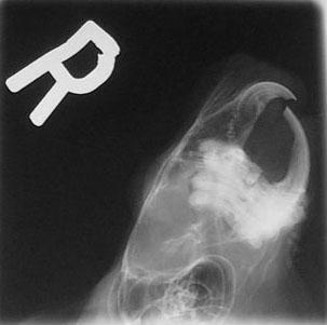

Below are x-rays of both a normal chinchilla and a chinchilla with malocclusion.

Normal

As can be seen, there is a major difference between the chinchilla with normal teeth and the one with malocclusion. The normal x-ray shows teeth meeting in a straight line with little or no curving of either the teeth or the roots. There is no evidence of the roots growing outside of the jaw line.